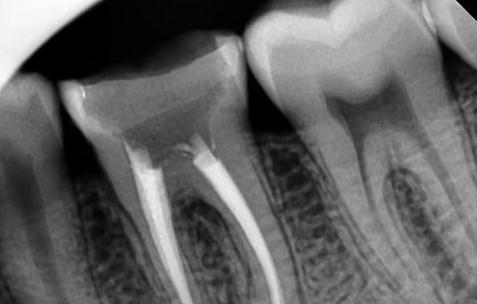

1、经过根管冲洗后,上药进行消毒,观察后没任何不适,就能钻开根管,扩大后预备完,就能到根管充填,将牙胶尖填满紧密,尽量避免超充欠充,但有些情况复杂,有的牙根弯曲,给根管带来一定难度,像这种要找经验丰富的医生处理。

2、这时根管结束,但牙体缺损还要再修复,超过一半牙体已经没了,要装个牙套,有条件建议二氧化锆全瓷牙,要是牙体量保留较多的,也可以嵌体修复,不用再磨牙,咀嚼效率比没根管完的牙体好很多。